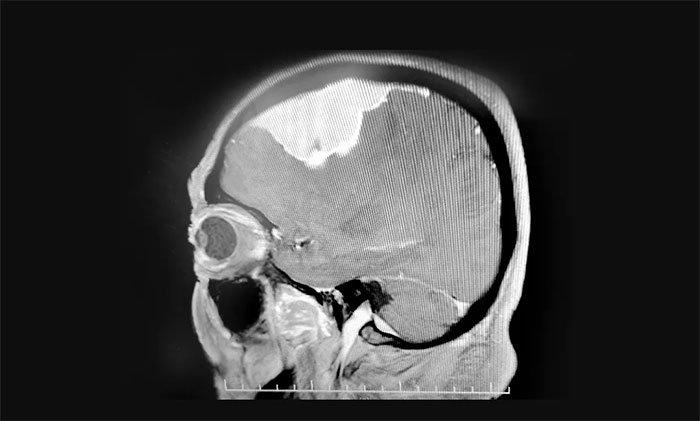

入院检查,头颅MRI提示:左侧额叶大脑凸面可见巨大团块状异常信号,周围可见明显水肿信号,胼胝体明显肿胀,临近左侧脑室受压向右侧移位,中线结构轻度右移,病灶大小约7.2×3.3×3.2cm。

▲ 肿瘤位于左侧额部